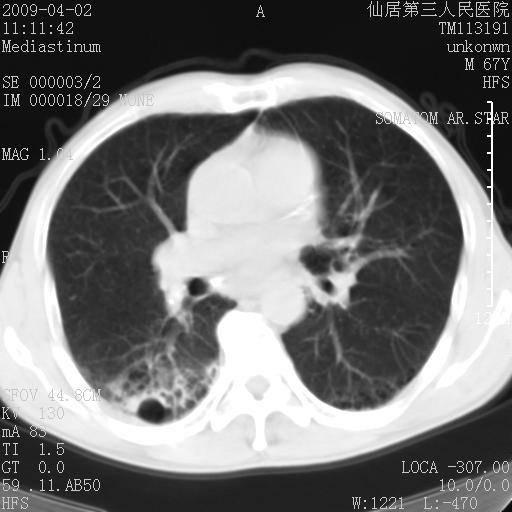

患者老年男性,乏力畏寒来诊,摄胸片示右下肺感染性病变,抗炎两周后复查胸片,无好转有进展。

后做ct平扫表现如下:

考虑右肺炎症可能性大,不除外细支气管肺泡癌

是否还要考虑肺间质纤维化,建议hrct扫描。

病灶呈蜂窝征,纵隔多个淋巴结肿大;肺泡癌需考虑

我认为普通的感染应该可以除外,间质性肺炎可能性较大,但如何解释纵膈的淋巴结肿大呢

考虑双肺间质性改变(间质纤维化?)伴右肺下叶感染。